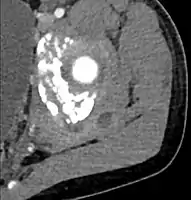

CT with IV contrast showing enlargement and heterogeneous hypodensity in the right pectoralis major muscle. A focal abscess collection with gas within it is present medially. There are enlarged axillary lymph nodes and some extension into the right hemithorax. Note the soft tissue and phlegmon surrounding the right internal mammary artery and vein. The patient was HIV+ and the pyomyositis is believed to be due to direct inoculation of the muscle related to parenteral drug abuse. The patient admitted to being a "pocket shooter"